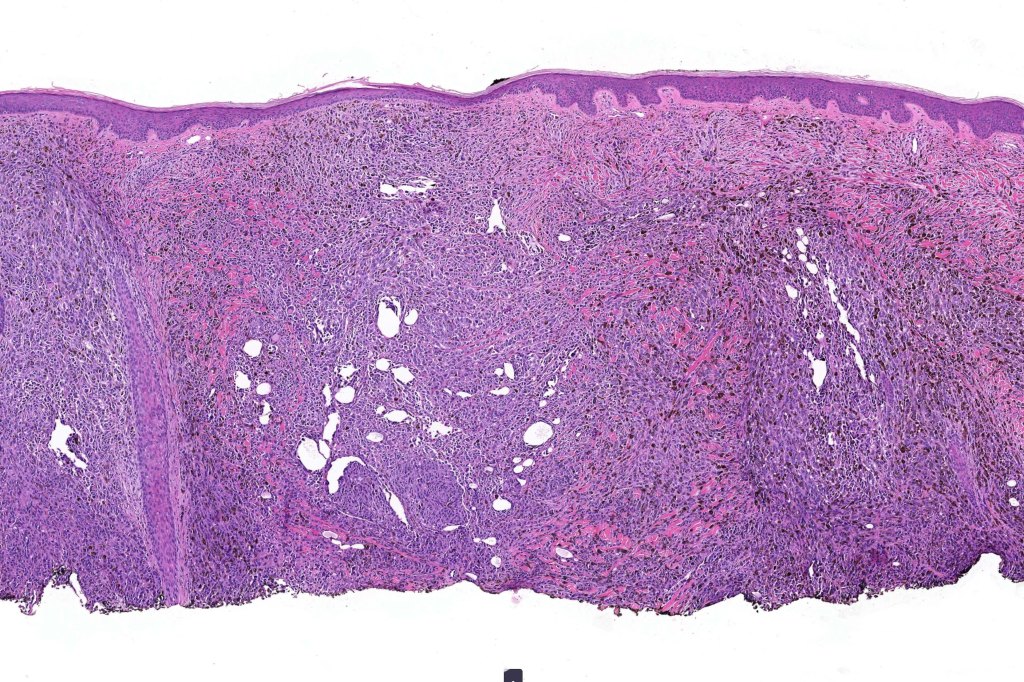

•Develops within a precursor lesion as one or more nodules of epithelioid or spindled cell melanoma

•The latter may show a dumbbell appearance at low power or scanning magnification

•Mutations in DNAQ or GNA11, Mutations in BAP1, SF3B1 & E1F1AX